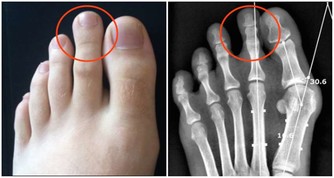

如果經常感覺到自己的嘴角有口瘡出現,而且容易全身疼痛,多半是某些重要的維生素缺乏了,特別是維生素D缺乏的時候應該高度重視。維生素D獲取充足能夠促進身體對鈣質的吸收,很多人全身疼痛,主要和鈣質缺乏有關,骨質疏鬆這種情況比較明顯,很多人就會感覺到全身產生疼痛感,甚至會有肌肉無力的感覺。

如果已經有這種現象,需要從飲食過程中獲取足夠的維生素D,平時還可以適當曬曬太陽,這樣可以促進身體對維生素D的合成,防止缺乏維生素D而出現全身疼痛表現。